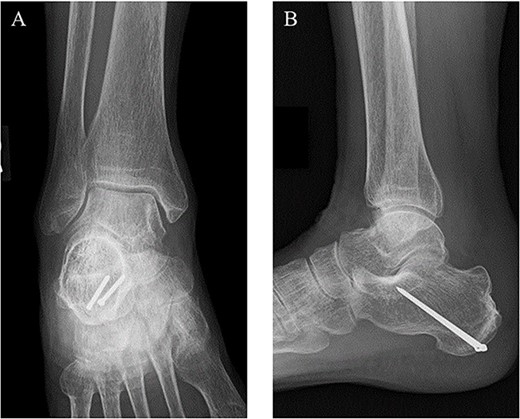

Postoperative (A) anteroposterior and (B) lateral ankle radiographs. The bone fragment was reduced and fixed using the combination of SLLS technique and ring pins.

Postoperatively, a non-weightbearing short leg cast was applied for 2 weeks, and when the cast was removed, active and passive ranges of motion exercises of the ankle were started. Partial-weightbearing was allowed at 2 weeks postoperatively, and full-weightbearing at 6 weeks postoperatively. At 3 months after the surgery, non-contrast CT showed complete bone union (Fig. 4). At 2 years after the surgery, she had no symptoms and dysfunctions (Fig. 5).